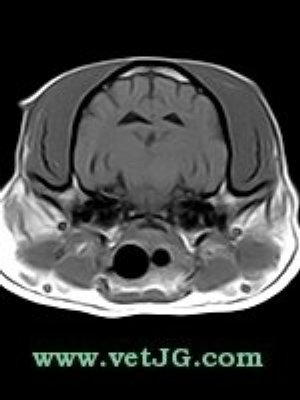

AXIAL

SAGITAL

DORSAL